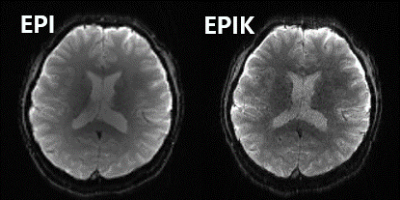

Figure 2 shows a reconstructed image from the EPI and EPIK scans at a nearly identical slice location. Although depicting lower SNR than the EPI scan, the EPIK scan shows a clearer delineation of anatomical structures around the boundaries between gray and white matters); the voxel volume of EPIK (1.95 mm3) is only nearly one-fifth of that of EPI (10.35 mm3).

Figure 2. Reconstructed EPI (Left) and EPIK (Right) scans at a representative slice location. The nominal spatial resolution of EPI and EPIK is 1.72 × 1.72 mm2 and 1.25 × 1.25 mm2, respectively.